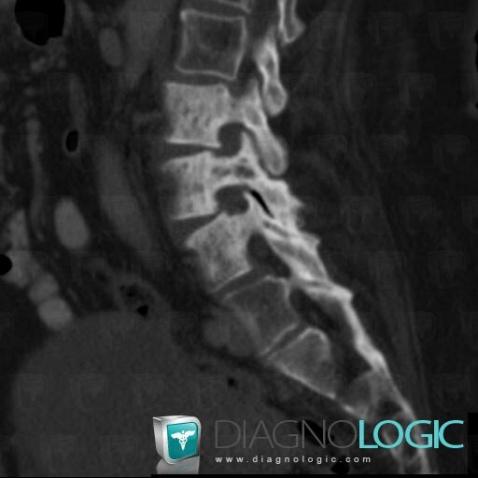

Metastasis, Vertebral body / Disk, CT

Here is the specific information in the key image above:

- Diagnosis Metastasis, Location(s) Vertebral body / Disk, with gamuts Focal area of sclerosis in a vertebra